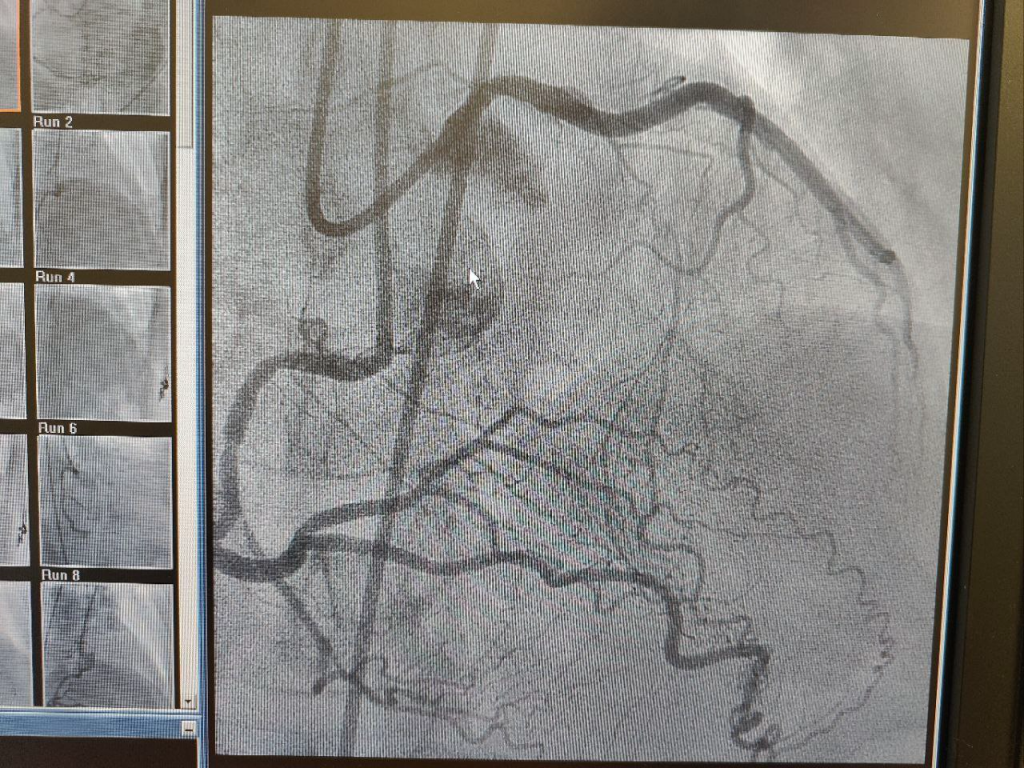

У 67-летней пациентки было диагностировано комплексное поражение коронарных артерий: хроническая окклюзия устья ПМЖВ, острая тромботическая окклюзия огибающей артерии и сохранённая проходимость правой коронарной артерии (ПКА). После экстренного стентирования инфарктзависимой огибающей артерии рентгенхирурги ЦГКБ №24 провели второй этап лечения — ретроградную реканализацию ПМЖВ через коллатерали ПКА с использованием двойного контрастирования. На четвёртые сутки после вмешательства пациентка была выписана домой.

«Ретроградная реканализация — это прорыв в интервенционной кардиологии. Метод позволяет работать с хроническими окклюзиями, которые раньше считались не поддающимися лечению без шунтирования. Мы обходим блокированный участок через коллатерали из соседних артерий, используя микрокатетеры и специальные проводники, а также двойное контрастирование. Эта процедура минимизирует риски и сокращает реабилитацию с нескольких месяцев до нескольких дней», — подчеркнул заведующий отделением рентгенохирургических методов диагностики и лечения ЦГКБ №24 Павел Леванин.

Ретроградная реканализация предполагает доступ к заблокированному участку артерии через коллатерали — мелкие ответвления от соседних сосудов. В данном случае врачи использовали коллатерали ПКА, что позволило пройти окклюзию ПМЖВ. Ключевую роль сыграло двойное контрастирование: одновременное введение контраста в правую и левую коронарные артерии улучшило визуализацию и снизило дозу контрастного вещества.